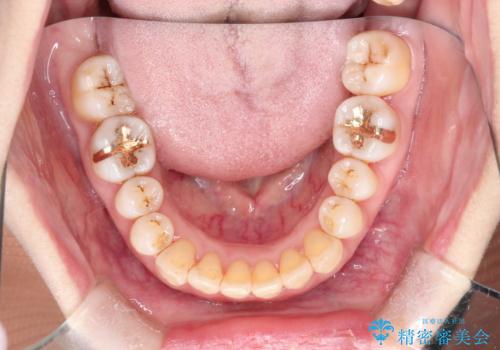

インビザラインによる矯正治療(非抜歯) 上下前歯の開き(開咬)と上下のガタつき(叢生)の改善

- 上下の前歯の開き(開咬)と上下前歯にガタつき(叢生)が見られます。

マウスピース矯正ではメカニクス的に開咬へのアプローチが容易です。

インビザラインの特色を生かした歯牙移動計画を作成し、非抜歯にて治療を行いました。

マウスピース枚数 初回36枚 + 追加26枚

概ね1年4ヶ月で治療完了しました。

マウスピース矯正は開咬(オープンバイト)に対して有利な治療メカニクスを持ちます。

当院独自の工夫を随所に盛り込み、狙い通りの治療結果が得られました。